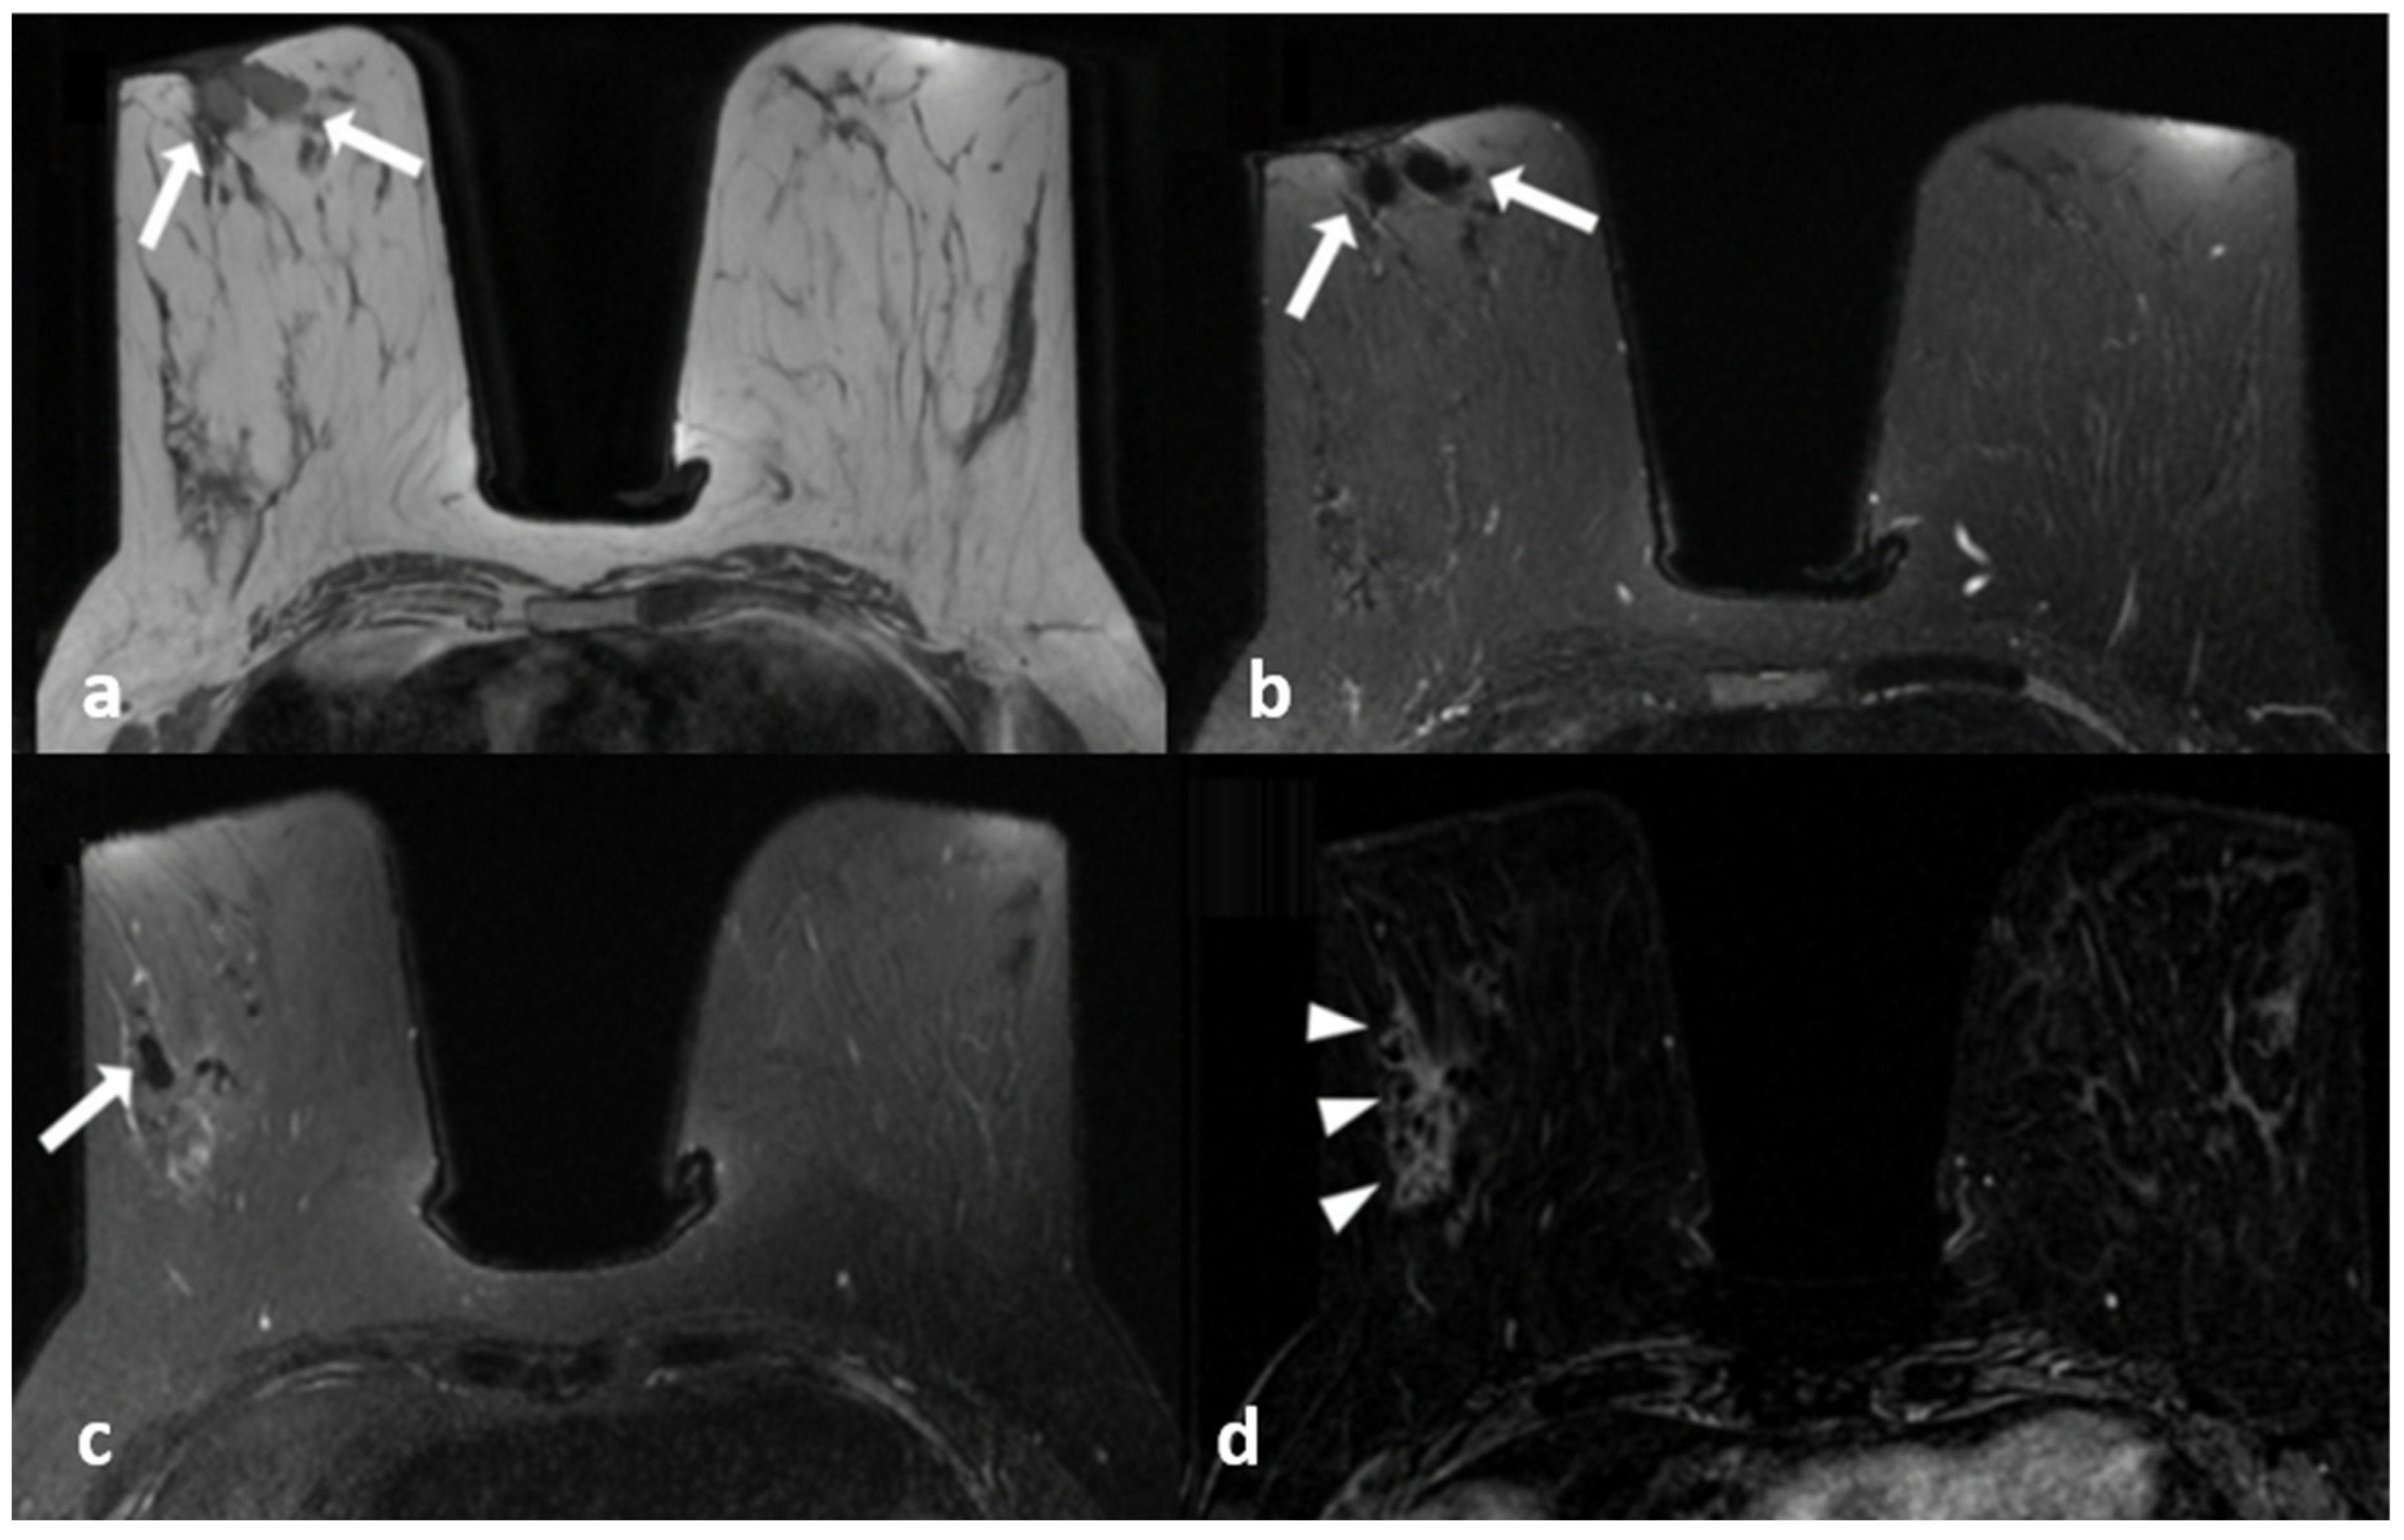

Architectural distortion was much more common in breast cancer (34.7%) compared to IGM (10.3%), (p = 0.001). IGM presented with focal skin thickening more often compared to breast cancer (p < 0.05), (Figure 1), whereas diffuse skin thickening was more common in breast cancer (p < 0.05). Dilated fat-containing ducts were more frequent in IGM (16.2%) compared to breast cancer (5.3%), but the difference was not statistically significant (Table 1 and Figure 2 and Figure 3). There was no significant difference between two groups in terms of amount of fibroglandular tissue, presence or absence of edema or the location of edema. Diffusion restriction based on both visual scale findings and ADC values showed no statistically significant difference (Table 2).

Figure 1.

A 39-year-old woman with histopathologically proven idiopathic granulomatous mastitis involving the left breast. (a) T1-weighted fast spin echo axial MR image of the patient reveals a parenchymal asymmetry in the upper outer quadrant of the left breast and skin retraction with focal skin thickening (arrow); (b) axial fat-saturated T2-weighted fast spin echo MR image, corresponding to (a) a small cystic lesion (arrow) within an area of signal increase in parenchyma associated with edema; a fistulae formation is seen as hyperintense linear area extending to the skin (arrowhead). (c) Axial contrast-enhanced subtracted image visualizes a heterogeneous enhancement in the parenchyma (star), at the same level with (a,b,d): axial diffusion-weighted image shows hyperintense restricted area corresponding to (a–c).